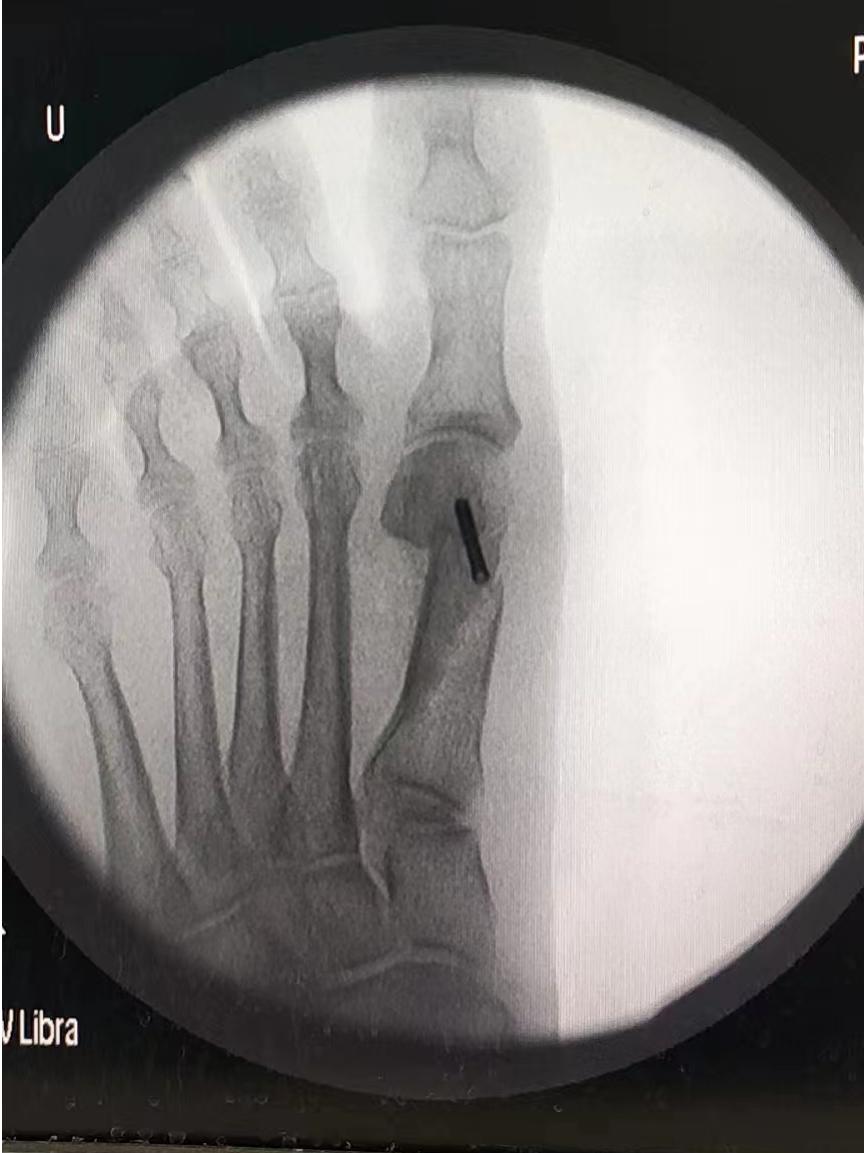

入院后,经过X片下的测量和术前相关检查后,与张阿姨进行手术沟通,拟定手术方案,最终决定针对张阿姨的情况给予拇外翻矫形术。

术后张阿姨姆囊部的疼痛及行走疼痛明显缓解,经过一段时间的休养,现已可以自由行走。“感谢你们让我彻底摆脱了拇外翻对我造成的多年困扰,现在我可以出门买菜,跳跳广场舞了”张阿姨握着医生的手激动的说。科普小知识